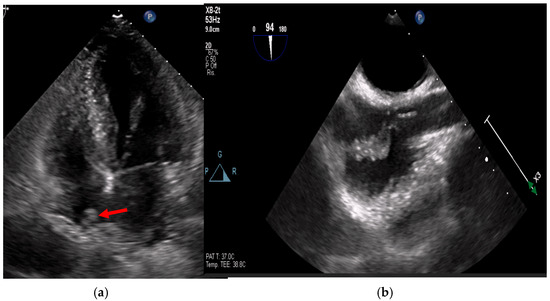

Multimodality Imaging in Infective Endocarditis: A Clinical Approach to Diagnosis

by Leonardo Brugiatelli, Francesca Patani, Carla Lofiego, Martina Benedetti, Irene Capodaglio, Pongetti Giulia, Francioni Matteo, Paolini Enrico, Nazziconi Marco, Kevin Maurizi, Furlani Giulia, Massari Arianna, Luciani Simone, Anselmi Benedetta, Gatti Chiara, Schicchi Nicolò, Fogante Marco, Tarsi Giovanni, Dello Russo Antonio, Di Eusanio Marco, Marini Marco and Fabio Vagnarelliadd Show full author list remove Hide full author list

Medicina 2025, 61(12), 2241; https://doi.org/10.3390/medicina61122241 - 18 Dec 2025

Infective endocarditis (IE) is a life-threatening condition with a rising incidence, demanding rapid and precise diagnosis. While echocardiography remains the cornerstone of initial evaluation, its limitations in complex cases—such as those involving prosthetic valves or cardiac devices—are well-known. This review synthesizes current evidence [...] Read more.

Infective endocarditis (IE) is a life-threatening condition with a rising incidence, demanding rapid and precise diagnosis. While echocardiography remains the cornerstone of initial evaluation, its limitations in complex cases—such as those involving prosthetic valves or cardiac devices—are well-known. This review synthesizes current evidence and guidelines to outline a practical, multimodality imaging approach for IE. We emphasize that integrating advanced techniques like cardiac computed tomography (CT) and [18F]-fluorodeoxyglucose positron emission tomography/computed tomography (FDG PET/CT) early in the diagnostic pathway, particularly in high-risk scenarios, significantly enhances diagnostic certainty, guides therapeutic decisions, and improves patient outcomes. A tailored imaging strategy, driven by clinical presentation and integrated within a multidisciplinary endocarditis team, is paramount for modern IE management. Full article

(This article belongs to the Special Issue Diagnosis and Treatment of Valvular Heart Diseases)

Show Figures

Figure 1